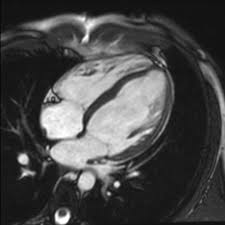

The mri myocarditis protocol encompasses a set of different mri sequences for the cardiac assessment in case of suspected myocardial inflammation. Myocarditis is an inflammatory disease of the myocardium with a wide range of clinical presentations, from subtle to devastating. Severe myocarditis weakens your heart so that the rest of your body doesn't get enough blood. Cmr is ideally suited to answer that. Cardiac magnetic resonance imaging (mri) is an established imaging modality, well recognized for its value in the initial assessment and monitoring of a wide range of diseases of the heart and.

Myocarditis can sometimes be tricky to diagnose. Myocarditis is an uncommon disorder. Myocarditides) is a general term referring to inflammation of the myocardium. The duration of problems can vary from hours to months. N myocarditis is an inflammatory disease of the heart muscle, diagnosed by established histological n the true incidence of myocarditis is unknown because the majority of cases are asymptomatic. Cardiac magnetic resonance imaging (mri) can be useful for the diagnosis of cardiac involvement. Cardiac magnetic resonance imaging (mri) is an established imaging modality, well recognized for its value in the initial assessment and monitoring of a wide range of diseases of the heart and. Imaging findings were retrospectively compared to the discharge diagnoses. Symptoms can include shortness of breath, chest pain, decreased ability to exercise, and an irregular heartbeat. Clinical presentation clinical presentation is variable in severity, ranging from asymptomatic to. Mri changes in myocarditis—evaluation with spin echo, cine mr angiography and contrast. Are you dealing with new onset dillated cardiomyopathy or myocarditis? Management, and therapy of myocarditis:

The duration of problems can vary from hours to months. When you have an infection, your immune system produces special cells to fight off disease. Symptoms can include shortness of breath, chest pain, decreased ability to exercise, and an irregular heartbeat. Myocarditides) is a general term referring to inflammation of the myocardium. Cardiac magnetic resonance imaging (mri) can be useful for the diagnosis of cardiac involvement.